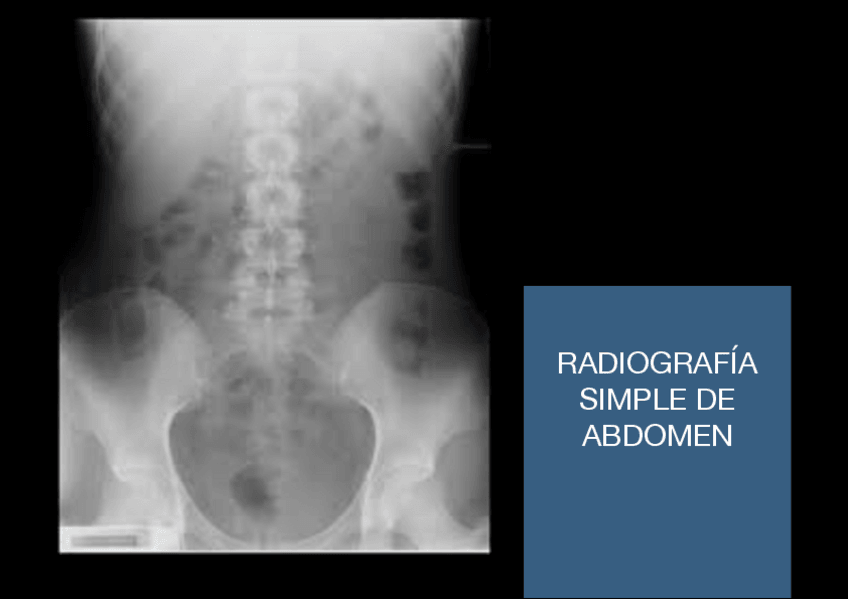

Radiología

He publicado nuevos apuntes de 3º radiología y medicina nuclear: Radiología

Placa-de-abdomen.pdf